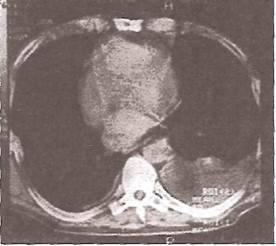

Еще более чувствительными методами выявления плеврального выпота являются ультразвуковое исследование органов грудной клетки (УЗИ) и компьютерная томография (КТ). На рис. 29 представлена КГ больного с правосторонним экссудативным плевритом. В задненижних отделах правого легочного поля (исследование проведено в положении пациента лежа на спине) заметно скопление жидкости с четкими границами и сдавление правого легкого (компрессионный ателектаз). Средостение несколько смещено в «здоровую» сторону

Рис. 29. Компьютерная томограмма больного с экссудативным плевритом.

Следует заметить, что при выполнении КТ по коэффициенту поглощения рентгеновского излучения обычно удается легко отличить скопление жидкости в плевральной полости и уплотнение самой легочной ткани, что нередко вызывает затруднения при проведении обычной рентгенографии органов грудной клетки.